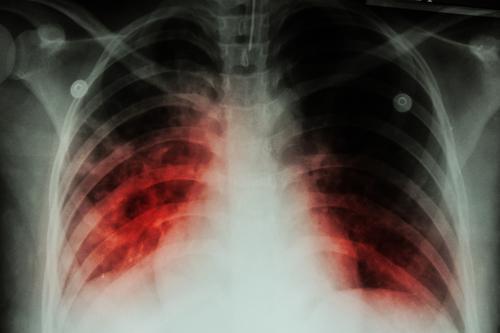

La campagne vise toute personne entrée en contact avec la victime plus de huit heures au cours du dernier trimestre. Les radiographies pulmonaires sont au cœur du dispositif. Les proches de la fillette devront en passer une dans l’immédiat et une seconde dans trois mois. Cette stratégie permet de mettre en place un traitement rapide.

Le diagnostic s’appuie sur une fièvre, et généralement une atteinte pulmonaire, mais pas toujours ; il peut aussi y avoir des méningites et des encéphalites. En général, elle n’est pas aiguë mais se prolonge. Cela explique aussi pourquoi le diagnostic est parfois posé avec un peu de retard.